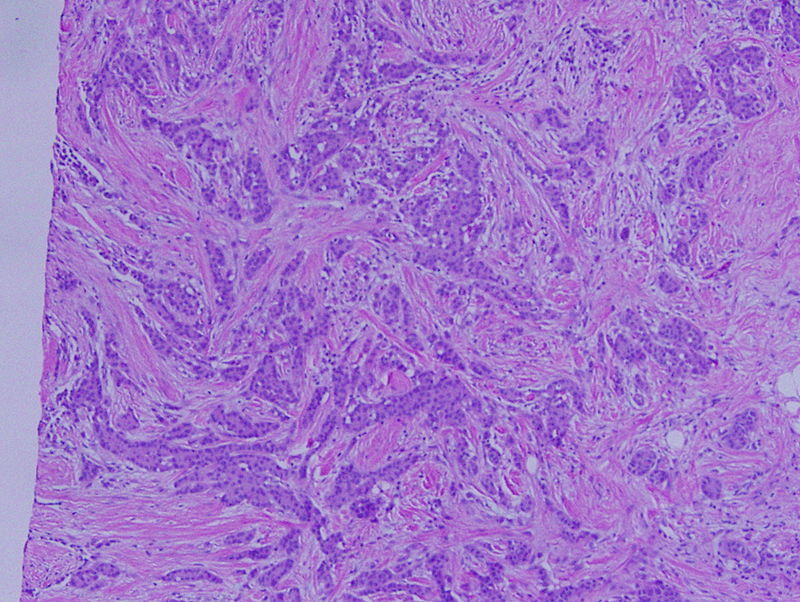

Histology of invasive ductal carcinoma shows haphazard ductal cells in a desmoplastic stroma.